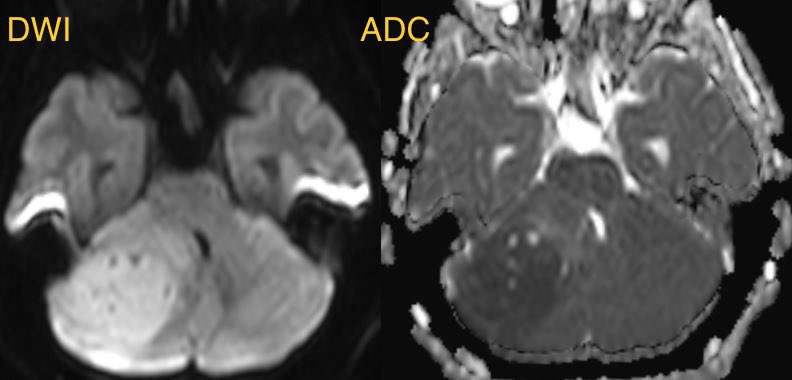

⭐️ Companion case of Lhermitte-Duclos - Unilateral cerebellar mass w/ striations due to hyperintense expanded fovea on T2 w/ normal signal intervening parenchyma

Typically there is no to little enhancement and high signal on DWI due to T2 shine-through w/ high signal on ADC x.com

💡 Both Lhermitte-Duclos & Medulloblastoma SHH can have a striated appearance! Use DWI/ADC, density on CT, & enhancement to distinguish!